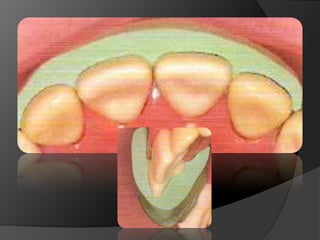

CARILLAS EN CERÁMICA: Alternativa menos agresiva cuando lo que se busca es el cambio de color o de forma en la superficie vestibular

Corona de Recubrimiento Completo Restauraciones Intracoronales Metálicas (A) o cerámicas (B)Corona de Recubrimiento Parcial

ONLAYCARILLA